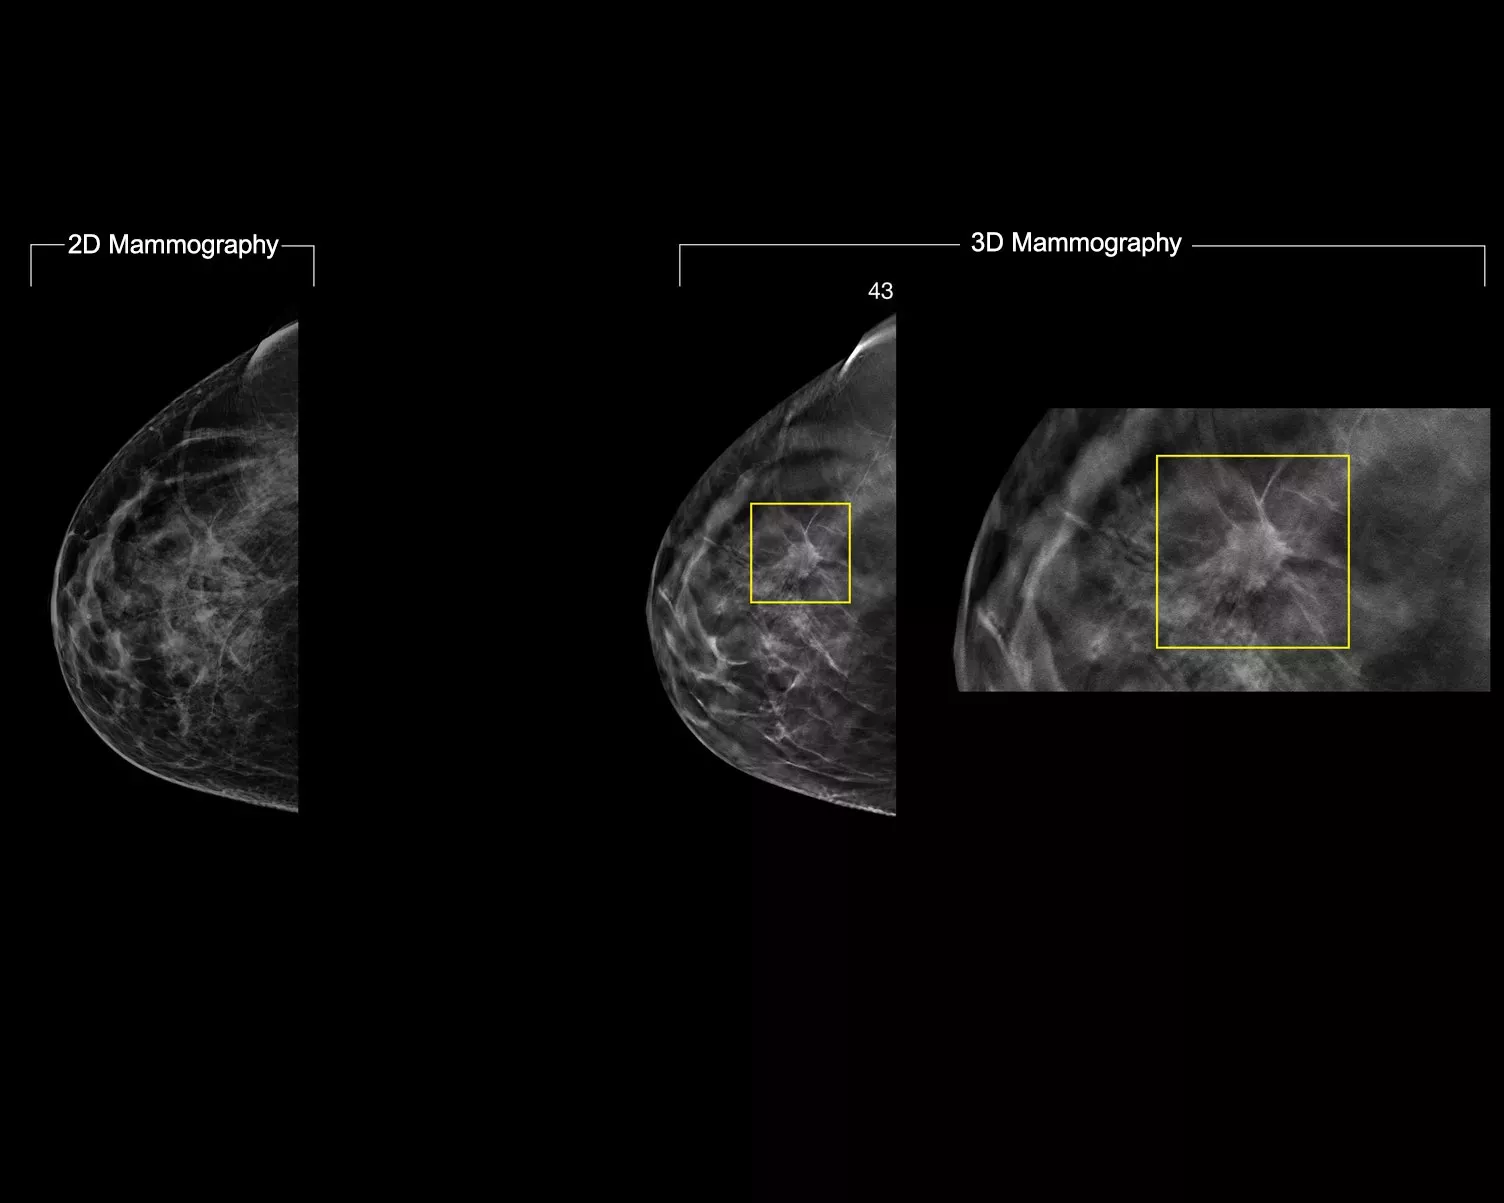

En deep-learning-algoritme designet til at hjælpe radiologers diagnostiske kapacitet og opdage brystkræft1-3 fra tomosyntesebilleder, der er optaget ved hjælp af Hologic Dimensions Mammography® systemer. Algoritmen lokaliserer læsioner, der sandsynligvis repræsenterer brystkræft, ved at søge i hvert snit af tomosyntesebilledsættet. Det mistænkelige område fremhæves til samtidig aflæsning på radiologens arbejdsstation for at bidrage til fortolkningen.

Algoritmen ser efter 3 hovedgrupper af mistænkelige læsioner: forkalkninger, masser, densiteter og forvrængninger og enhver kombination af disse læsioner. Output kan variere på forskellige læsearbejdsstationer.